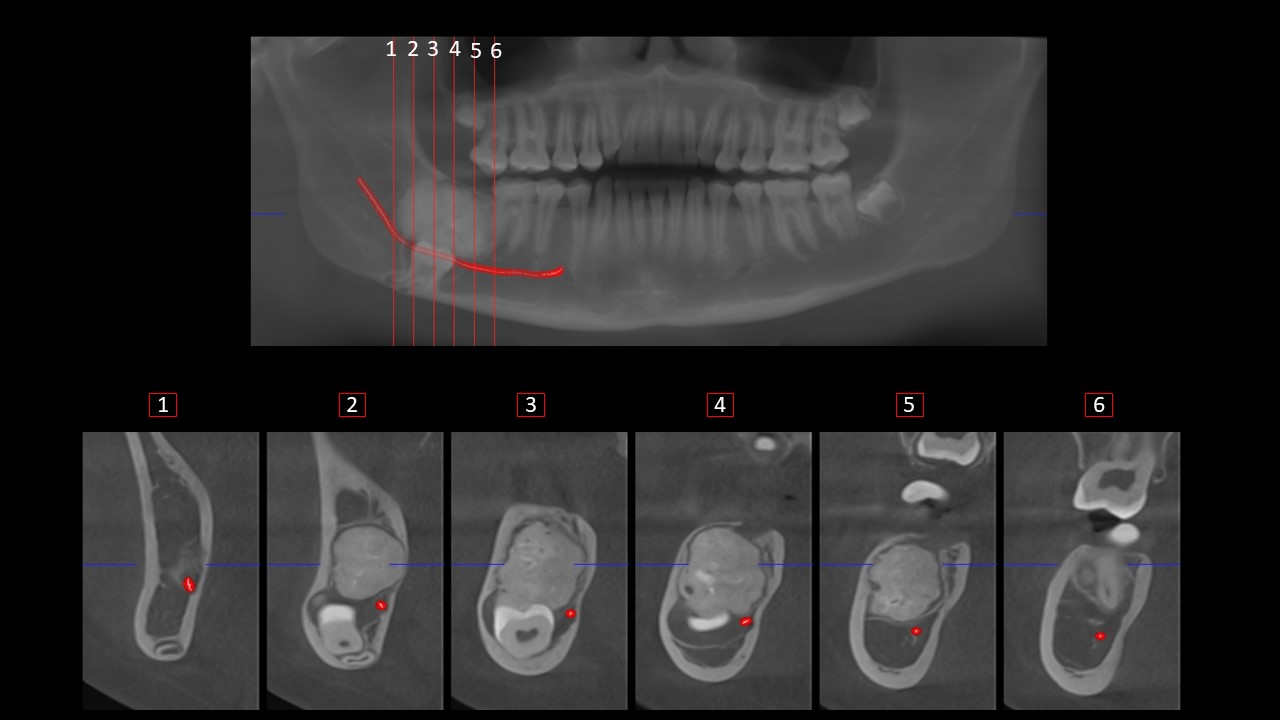

Figura 5

En los cortes transaxiales (Figura 5)(corte 4 y 5) se observa un canal corticalizado e isodenso, que comunica la masa con la cima del reborde alveolar, denominado tracto gubernacular el cual sirve como guía de erupción dental en las piezas en desarrollo, cuyo hallazgo implicaría que estamos ante una lesión de origen odontogénico. Signos imagenológicos a descartar odontoma complejo.